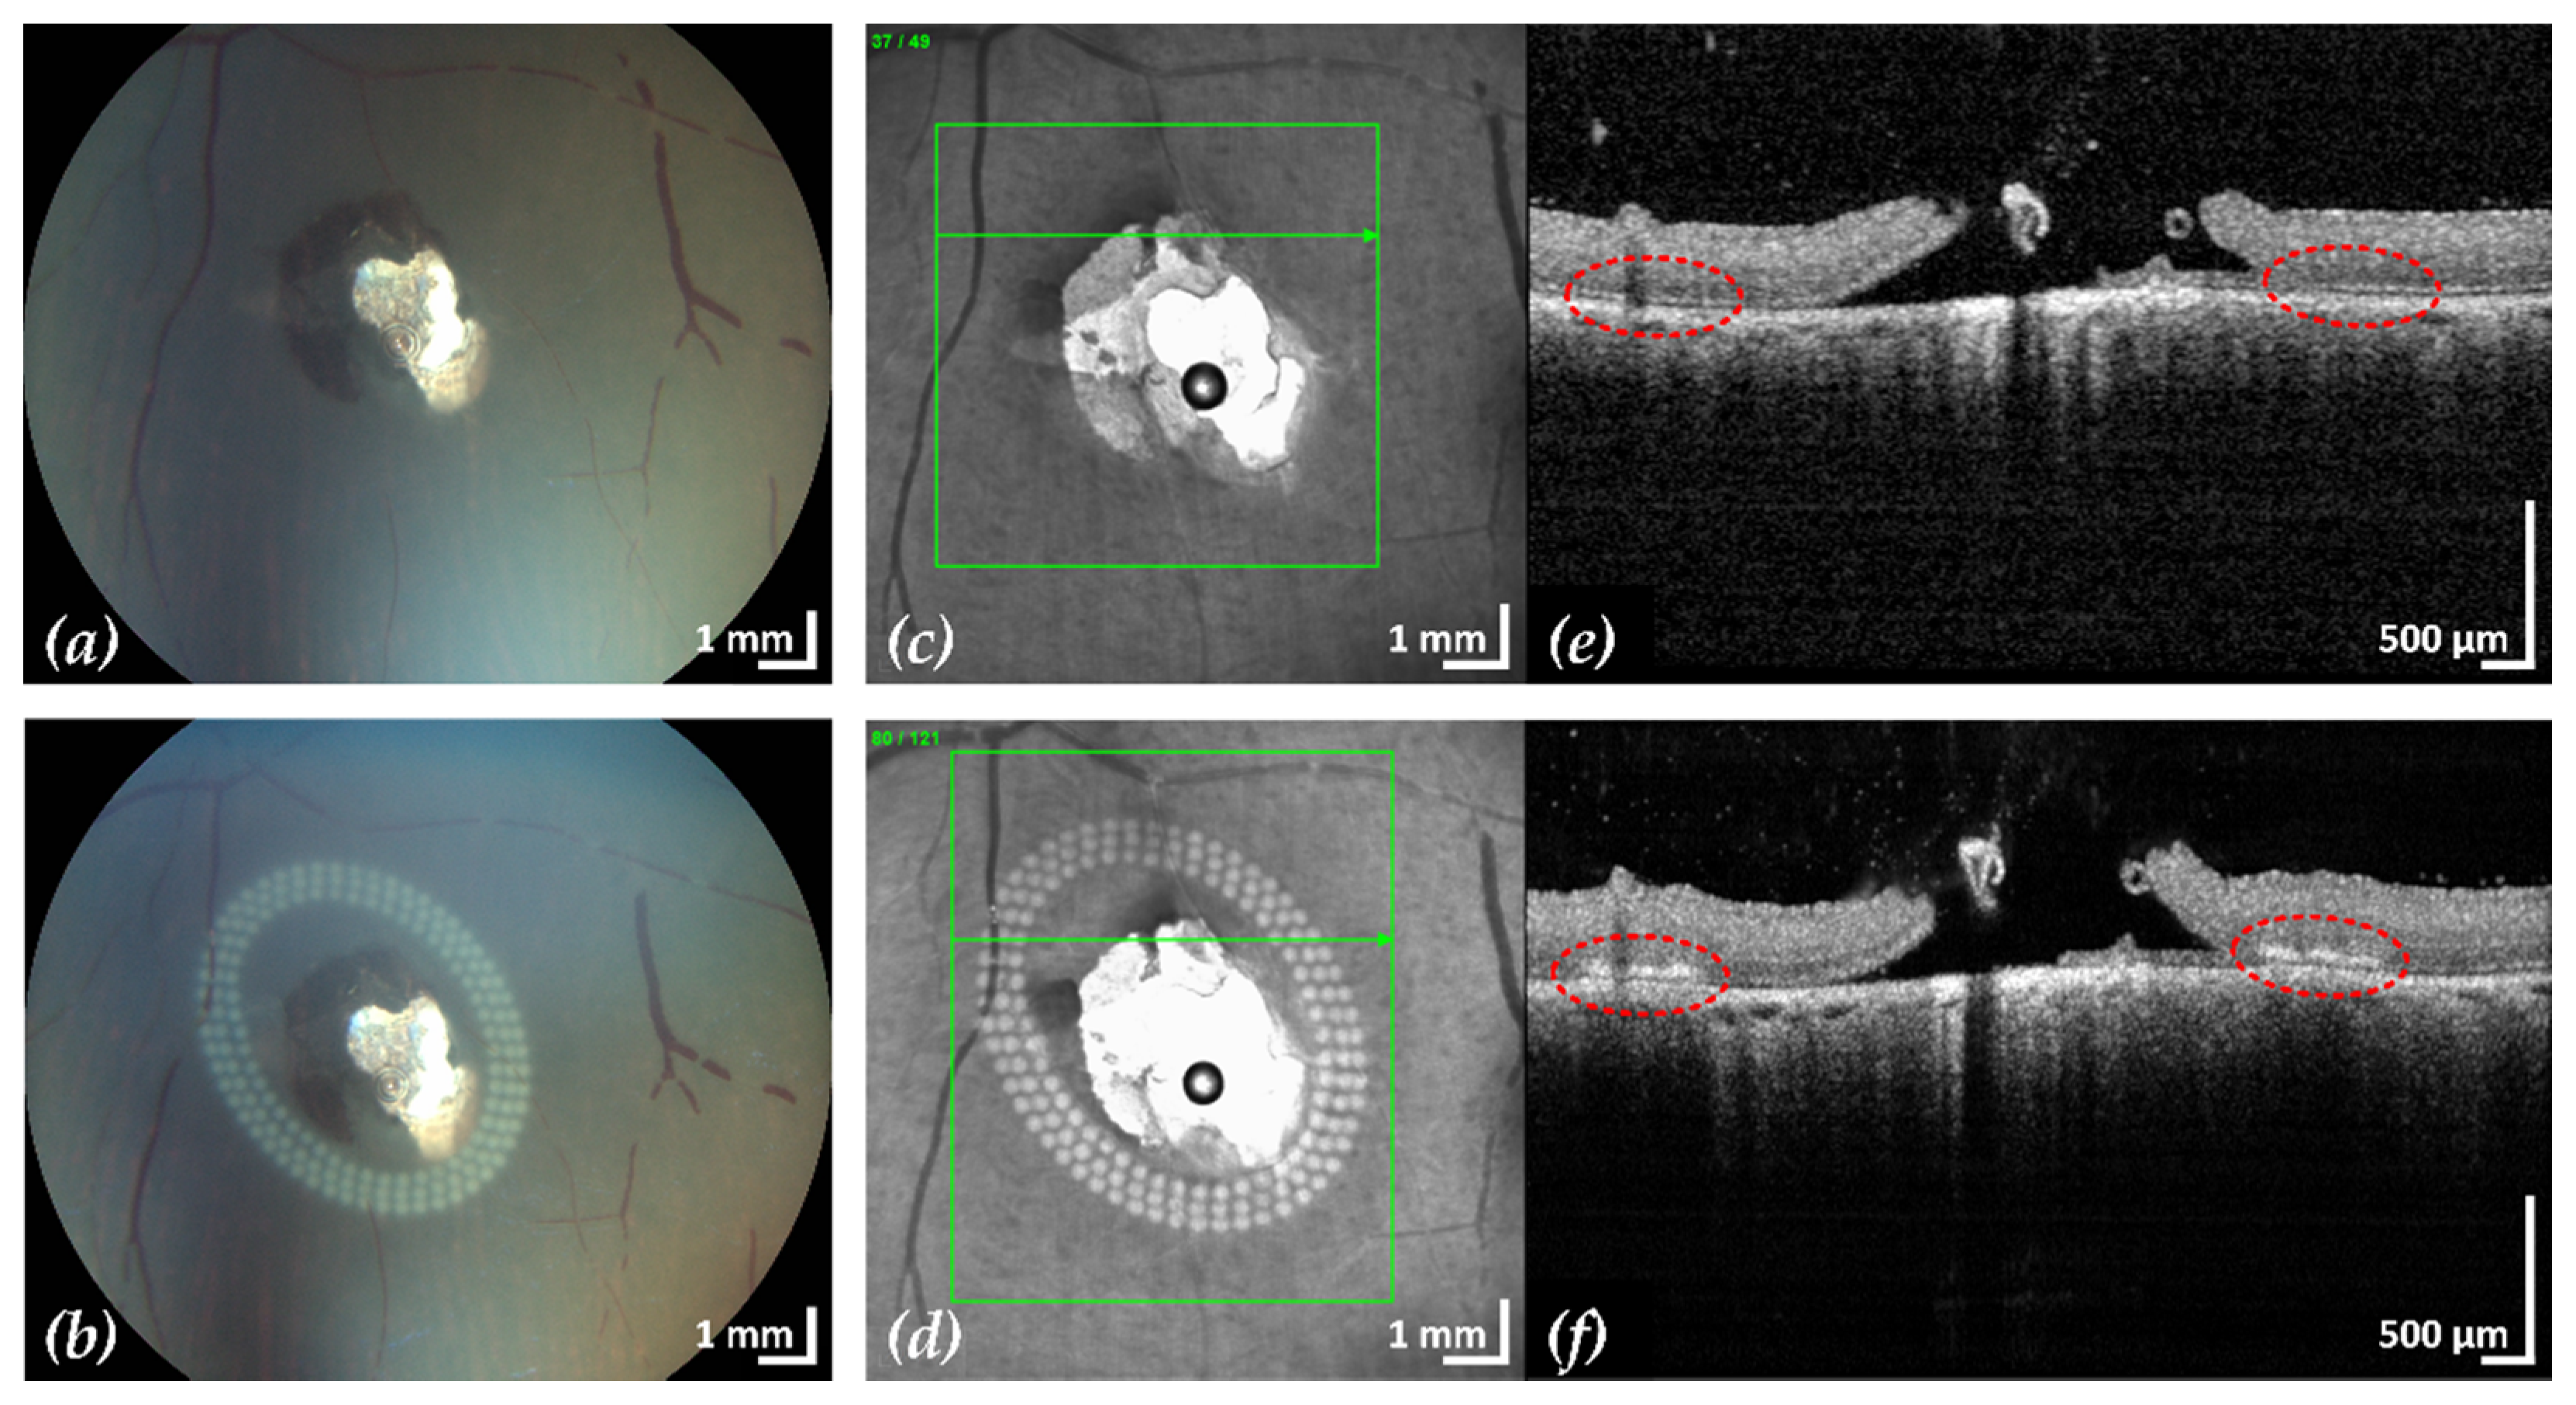

Figure 4. Example 1: treatment outcome in ex-vivo porcine eye with artificially induced retinal break (area of retinal break and adjacent RD: 25.2 mm2). Fundus photographs before (a) and after (b) treatment, infrared scanning laser ophthalmoscope images before (c) and after (d) treatment with the corresponding SD-OCT B-scans (e,f). A total of 200 lesions were applied in three rows with a radial and tangential (point to point) distance of 200 µm and 300 µm, respectively. The LPC treatment time was 4:19 min. The effect of LPC treatment is visible in (b,d) as spots of whitened tissue and in (f) as ruptures in the retina at the treatment sites (red).

After treatment, CFP and cSLO showed the typical tissue whitening caused by LPC lesions around the retinal break (Figure 3). The SD-OCT B-scans showed hyperreflectivity of the retina at the laser application sites, indicating successful treatment. In most eyes, the laser treatment was entirely applied in regions of still attached NSR, the goal of successful laser retinopexy to seal the break. Two exemplary results are shown in Figure 4 and Figure 5.